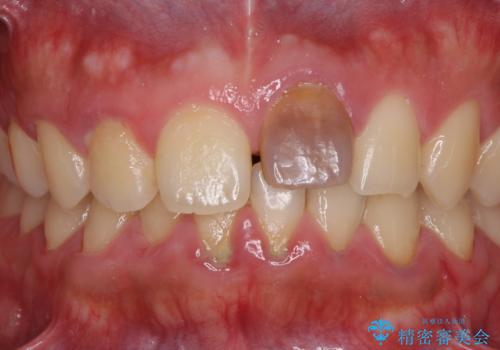

- 中学生の時にぶつけて以来、そのままにしていたところ前歯が変色してきたとのことで来院された患者様です。

レントゲン写真より、歯の中の神経組織が失活していることが分かったため、根管治療、ファイバーコアによる土台築製を行い、オーダーメイドタイプのオールセラミッククラウンにて補綴することとしました。